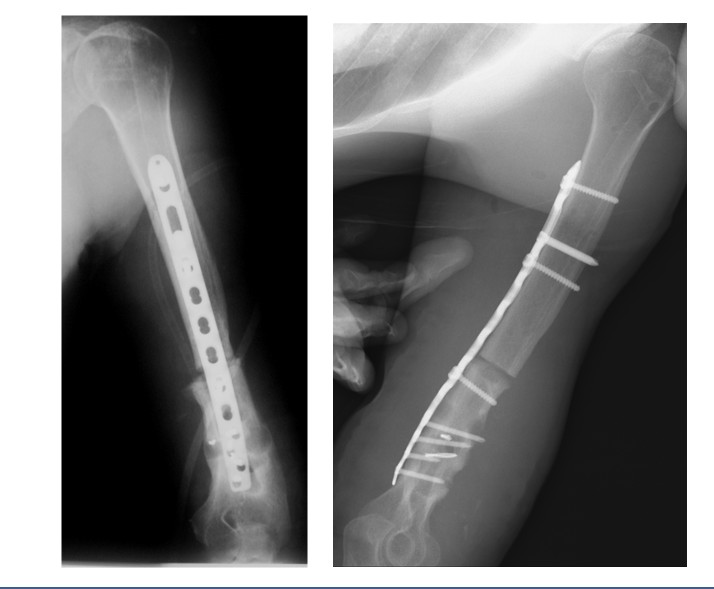

Пациент 29 лет. Диагноз: несросшийся перелом левой плечевой кости, состояние после остеосинтеза штифтом.

Пациент 29 лет. Диагноз: несросшийся перелом левой плечевой кости, состояние после остеосинтеза штифтом Этап 1: резекция несращения, остеосинтез пластиной.

Рентгенограммы после операции по васкуляризированной костной пластике